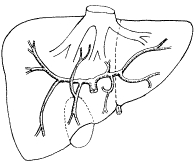

左右肝管汇合形成肝总管。右肝内胆管分为右前叶肝管、右后叶肝管;左肝内胆管分为左内叶肝管及左外叶肝管。肝内胆管结石易发生于左肝管起始部,肝管狭窄伴管腔扩张、堆积结石。还多见于右前、后肝管汇合成右肝管开口处,胆管结石堆积。正常胆道在PTC、ERCP时直径0.7~1.0cm,管径<0.06cm考虑硬化性胆管炎,管径>1.0cm考虑胆道梗阻,病因为胆管结石、肿瘤、乳头良性狭窄等。肝内胆管轻度狭窄指胆管最大直径超过最小直径1倍以下。重度狭窄指胆管最大直径超过最小直径1倍以上。